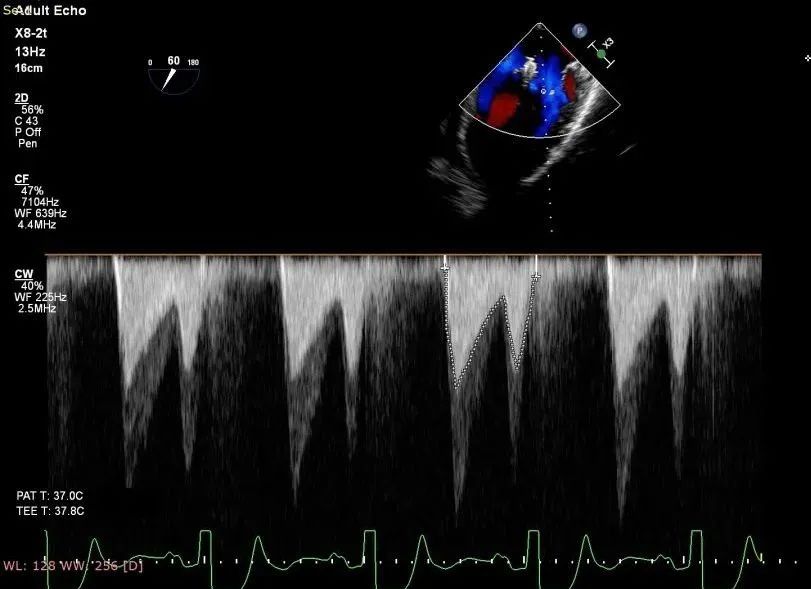

术后二尖瓣反流评估

术后结果